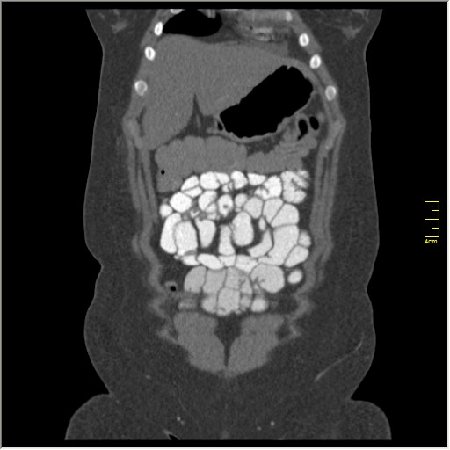

Демонстрационные изображение, оцените возможности метода! Толщина среза реконструкции 0.5-1 мм.